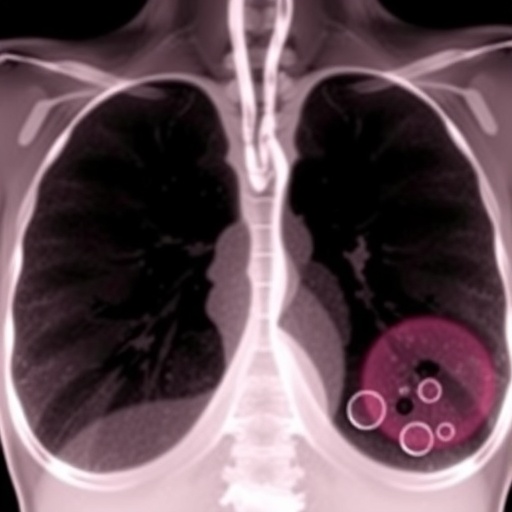

To rigorously explore this phenomenon, investigators employed engineered mouse models bearing prostate tumors that developed resistance to docetaxel after repeated exposure—an experimental system closely mirroring clinical resistance patterns. Analyses revealed significantly higher FOXJ1 expression in chemoresistant tumors versus those responsive to treatment. Manipulating FOXJ1 expression in prostate cancer cells further validated its role: overexpression induced resistance, while knockdown of FOXJ1 sensitized tumors to taxanes, underscoring its pivotal influence.

The molecular underpinnings of FOXJ1-mediated chemoresistance appear to involve a coordinated regulation of a broad network of genes linked to microtubule formation and stabilization. Through transcriptomic profiling, the team identified multiple downstream targets controlled by FOXJ1, collectively modulating cytoskeletal architecture and thereby obstructing taxane action. This suggests FOXJ1 functions as a master regulator orchestrating structural adaptations that cancer cells exploit to escape chemotherapy-induced cytotoxicity.

Crucially, the translational impact of these findings was reinforced by human patient data. Tumor biopsies from taxane-treated patients showed FOXJ1 gene amplification was more prevalent in those displaying poor therapeutic response. Large clinical trial datasets also confirmed that high pre-treatment FOXJ1 expression correlates with diminished survival benefits when docetaxel is incorporated into hormone therapy regimens, highlighting its prognostic relevance.